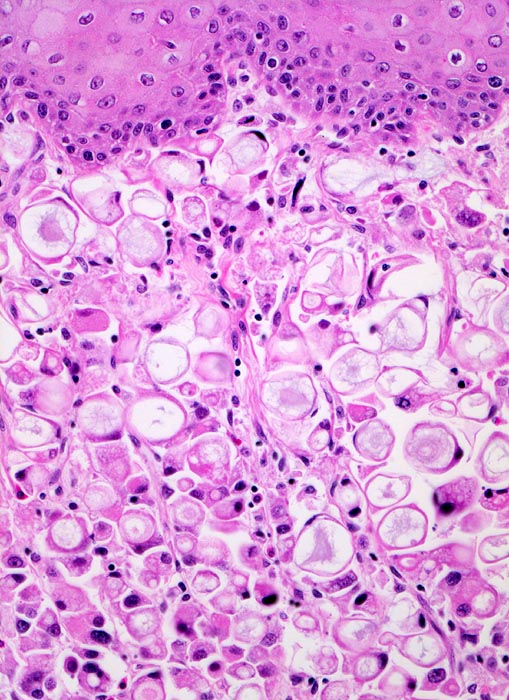

Siegelringzellkarzinom des Magens: Tumorinfiltration des Ösophagus

Der Tumor breitet sich submukös im Ösophagus aus. Die Ösophagusschleimhaut über dem Tumor ist intakt. Der Tumor besteht praktisch ausschliesslich aus Siegelringzellen mit unterschiedlich grossen Schleimvakuolen, die den Kern zur Seite drängen.

Magenkarzinome, die zu mindestens 50% aus Siegelringzellen bestehen, werden gemäss WHO als Siegelringzellkarzinome bezeichnet.